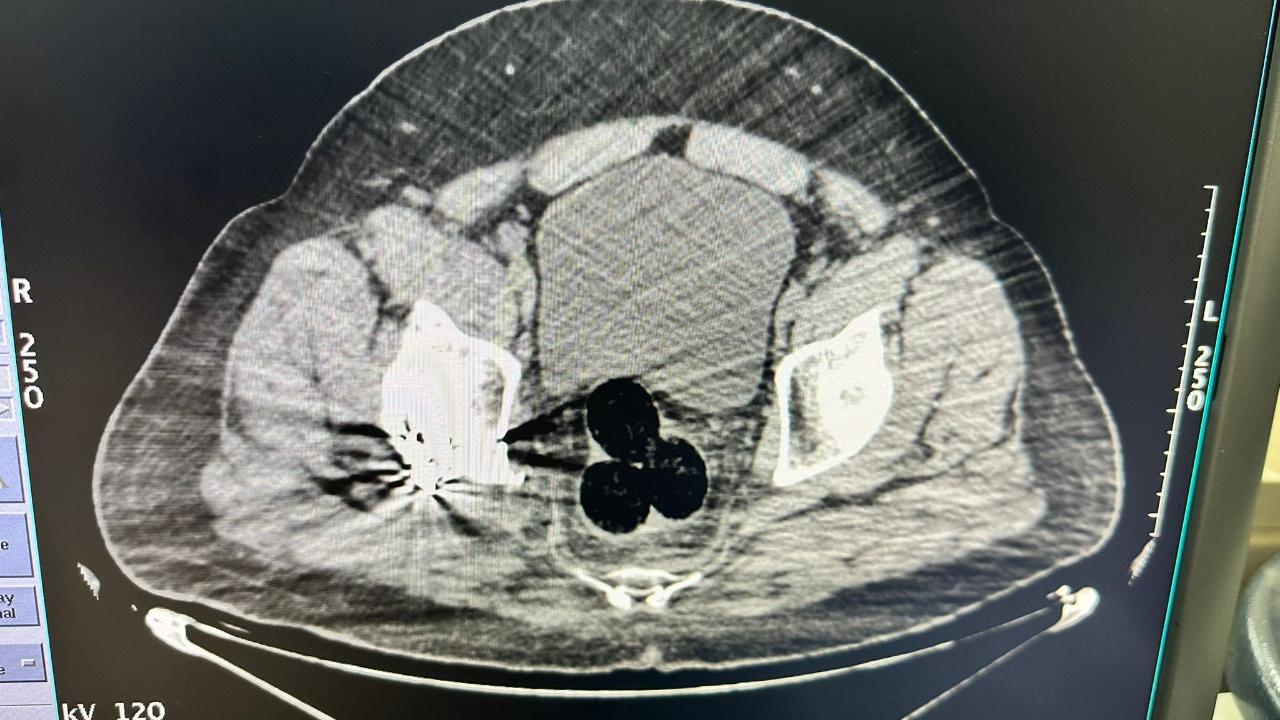

İran'dan Türkiye'ye giriş yapan ve vücut boşluklarında narkotik madde sevkiyatı yaptığı değerlendirilen yabancı uyruklu bir şahıs, titizlikle yürütülen çalışmalar sonucu Iğdır'da yakalandı. Şahsın radyolojik görüntüleme yöntemiyle yapılan iç beden muayenesinde, vücut boşluklarında gizlenmiş 3 parça yabancı cisim olduğu tespit edildi. Bu cisimler çıkarılarak el konuldu.